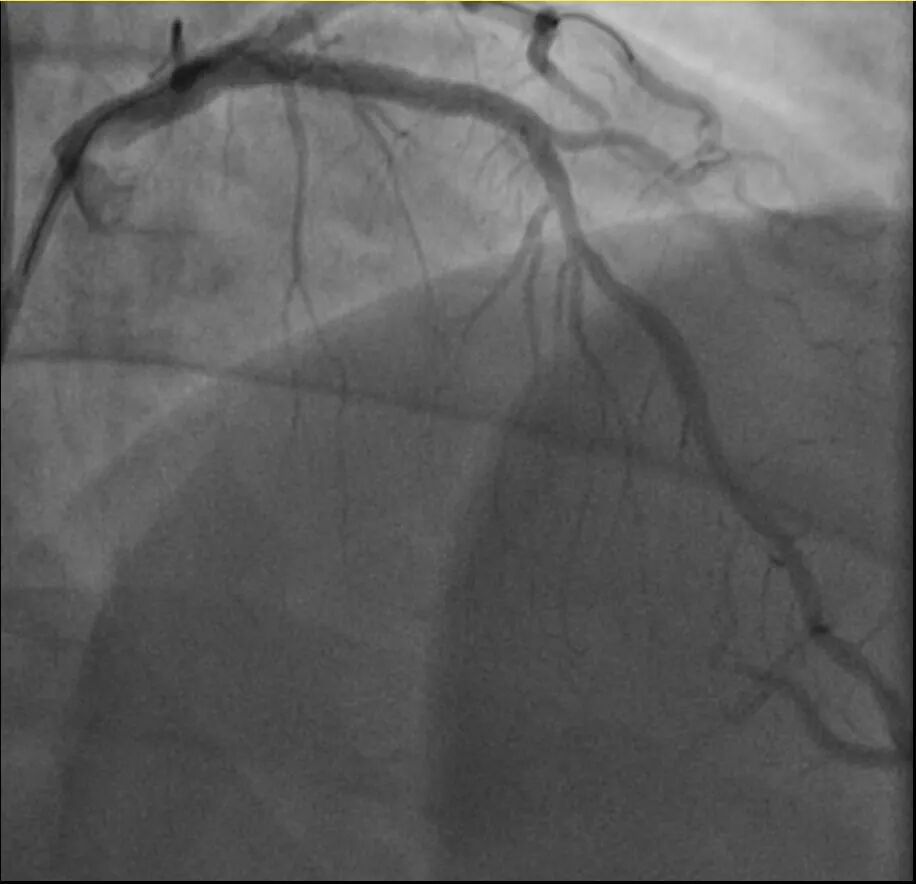

他的血糖一直偏高,服药后控制不佳,但年轻的钱先生并没有太上心。周末,他和孩子爬了一座山,隔天,钱先生就因突发胸骨中段压榨性疼痛被送到了急诊,最后被证实也是心梗——心脏三支主要血管之一回旋支远段次全闭塞。

浙江医院心血管内科翁莹政医师介绍,这位患者来院时血糖12.79mmol/L(正常空腹值应该在3.9~6.1mmol/L),甘油三酯也超标。三高(高血压、高血脂、高血糖)是导致动脉粥样硬化(包括心脏的冠状动脉)的主要危险因素,在冠状动脉粥样硬化早期,血管狭窄可能并不严重,仅当血管狭窄到一定程度时,在运动、情绪激动等情况下,心肌耗氧量增加,就可能造成心梗等急性心肌缺血事件。所幸经过汤益民团队的及时介入治疗,钱先生也转危为安。